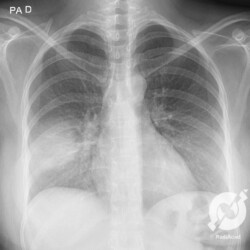

Os agentes etiológicos infecciosos são variados (bactérias, vírus, fungos, parasitas…), mas o que ocorre nos pulmões durante uma infecção por qualquer tipo de agente é a substituição do ar alveolar por secreção (pus, muco, eventualmente sangue ou necrose…) e com isso a manifestação radiográfica vai ser a mesma já que todas estas secreções apresentam a mesma densidade radiográfica: partes moles.

E o nome dado a esta alteração radiográfica que corresponde à substituição do ar alveolar por líquido é a consolidação alveolar.

Uma consolidação alveolar é, por definição, uma opacidade (imagem densa, branquinha) homogênea ou às vezes heterogênea (pela presença de calcificações ou cavidades), de limites mal definidos, exceto quando toca a pleura da parede ou das cissuras pulmonares. É um termo usado tanto em radiografia, como em tomografia computadorizada. Na tomografia, um outro termo é usado: vidro fosco, que é uma opacidade (branquinha mas não tanto como a consolidação), que borra o pulmão mas deixa ver os vasos de permeio (igual bigode de adolescente: dá pra ver todo o fundo).

Nós vamos mostrar aqui um pequeno apanhado de pneumonias de variados agentes, em diversos segmentos e lobos pulmonares, com extensões variadas. O objetivo é identificar o padrão radiológico de consolidação alveolar e não determinar o agente infeccioso, isso vai ser assunto para mais adiante. Aliás já antecipo que é fundamental saber localizar a lesão, porque alguns destes bichos gostam de determinados segmentos, alguns tumores também têm as suas preferências, então localização é fundamental. Se localização não fosse importante, um apartamento na beira do mar sairia o mesmo preço de um apartamento de frente pra BR-101, concordam?

Seguem alguns dos nossos casos de pneumonia para vocês treinarem os olhos e não se apavorarem nos plantões.